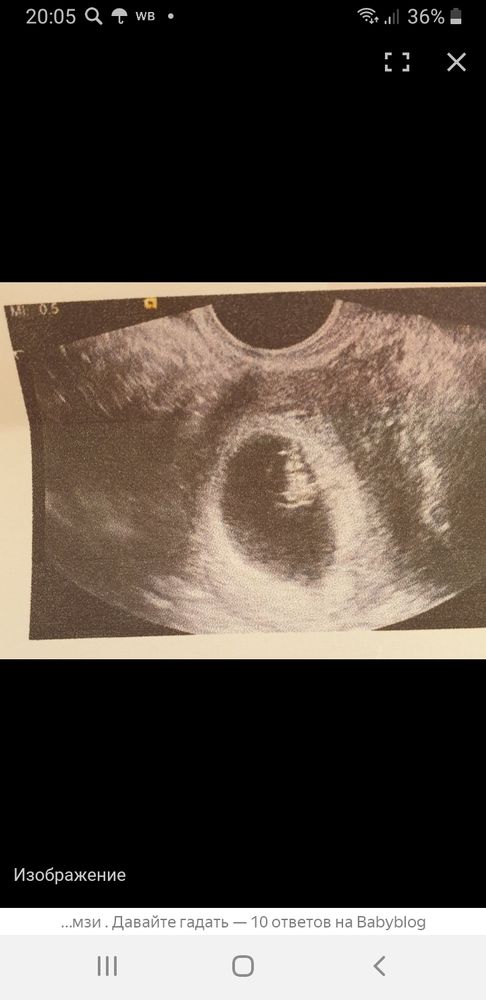

Настасья, вот мой Горошек на этом сроке. Всё писали тоже девочка, ан нет... Мальчик...

Мария Солнце, спасибо 😙У тебя тут мальчишка,хорион идёт вправо, так что совпало! Просто многие неверно трактуют метод,в нём надо немного разобраться) Я раньше тоже так, поверхностно по нему шарила, сейчас вот, вроде разобралась более менее)